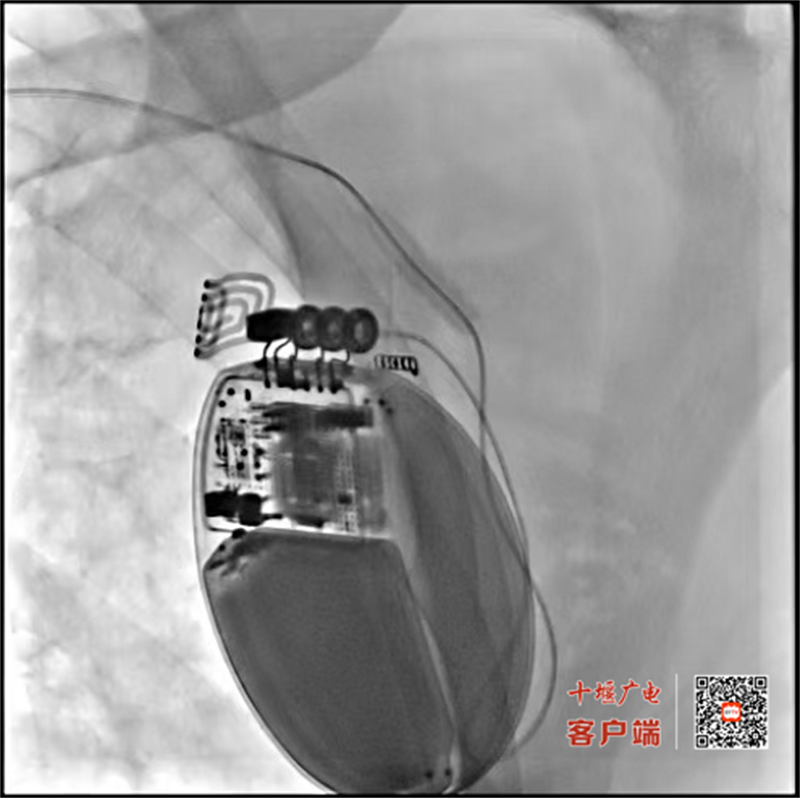

据悉,该患者入院前已在院外经历了三次生死劫难——三次突发性室性心动过速,这意味着他的心脏曾多次骤然陷入无效且致命的狂跳之中,每一次发作都无异于一次心源性猝死的预演,生命悬于一线。经紧急抢救暂时脱险后,患者赶到十堰市人民医院心内科2病区门诊求助。接诊的袁良俊技术主任凭借丰富的临床经验,意识到患者时刻处于下一次心脏猝死的高风险之中,当即开通绿色通道,将其收入心脏监护病房,进行严密监护和全面评估。检查结果令人揪心:患者不仅心功能极差,还同时伴有肝肾功能衰竭和严重感染。面对复杂的病情,心内科迅速组织多学科协作,吴三五主任亲自带队查房,组织全科讨论,为患者制定了“先稳定内环境,再行根治手术”的缜密方案,而为患者植入ICD是预防心源性猝死最有效的手段。ICD被称为“植入体内的救命神器”,能够24小时不间断地监测心率,一旦发现致命性室速或室颤,便能立即在体内进行自动除颤,有效终止恶性心律失常,为患者建立起一道坚实的生命防线。经过积极的抗感染、保护脏器功能及纠正心力衰竭等综合治疗,患者的感染得到控制,肝肾功能及心功能等关键指标逐步改善,达到了可耐受手术的相对稳定状态,为ICD植入赢得了宝贵的时机。在吴三五主任与李波副主任的全程指导下,吴悠博士与向阳医生凭借精湛的技艺和丰富的经验,精准、顺利地将ICD植入患者体内。手术过程顺利,术后在医护团队的精心照护下,患者恢复迅速,再未发生恶性心律失常事件,摆脱了猝死的阴霾。事后,患者一家特意定制了一面锦旗,寄送到心内科2病区医护团队手中。患者在电话中动情地说:“我们人虽然出院了,但这份救命之恩永远不能忘,是你们给了我第二次生命!”

植入式心脏转复除颤器(ICD)是一种小巧、精密植入于皮下(通常位于锁骨下方)的电子装置,它通过连接的电极导线持续监测患者的心律。其核心功能在于两大“绝技”:

1. 抗心动过速起搏(ATP):当监测到频率较快的室性心动过速(VT)时,ICD会首先启动一种温和的方式,发放一阵快速的起搏脉冲,尝试“超速抑制”并终止心动过速,患者通常对此无感。

2. 高能量电击除颤:若室速过快或恶化为最致命的室颤(VF),或ATP治疗无效,ICD会在数秒内自动充电,释放一次高能量电击,使心脏瞬间“重启”,恢复正常节律,从而挽救患者生命。

此外,现代ICD也具备常规起搏器的全部功能,可有效治疗心动过缓。对于心梗后、心力衰竭等心功能严重受损以及有过晕厥病史的高危患者,ICD是目前国际公认的预防心源性猝死的“金标准”疗法。(通讯员 杨柳)